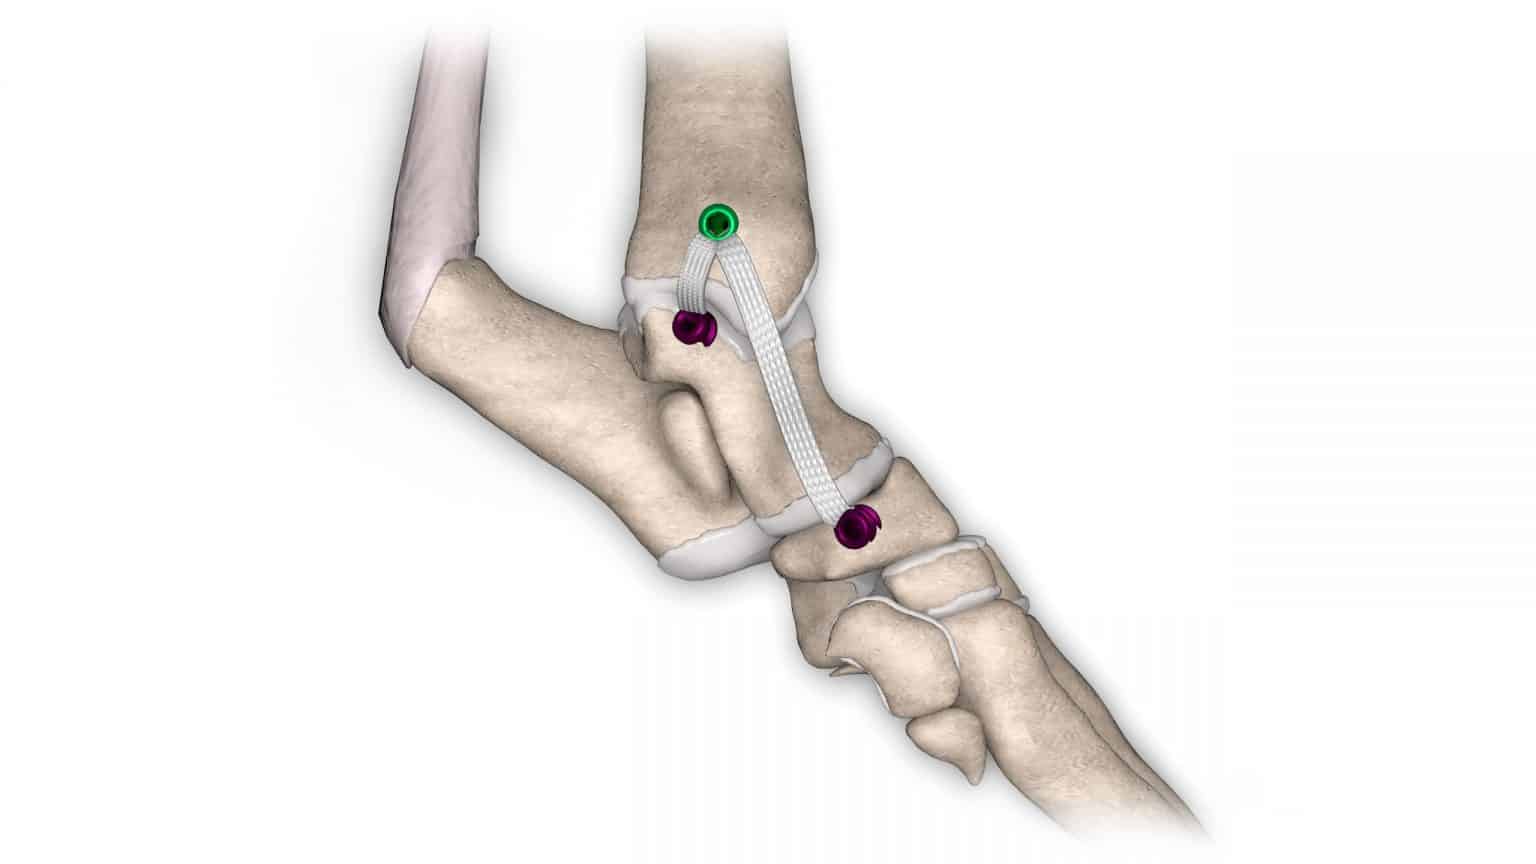

V případě ruptury kraniálního zkříženého vazu umožňuje ExtraTape® extraartikulární rekonstrukci co nejblíže izometrii původního vazu, čímž rychle a trvale stabilizuje koleno bez uzlů a zvlnění, což je slabina tradičnějších technik extraartikulární stabilizace. Ty jsou zde nahrazeny pevným ukotvením kosti pomocí interferenčního šroubu.

Řešení, které respektuje původní anatomii, obnovuje funkci postiženého vazu a je dostupné v rámci otevřené nebo artroskopické chirurgie.